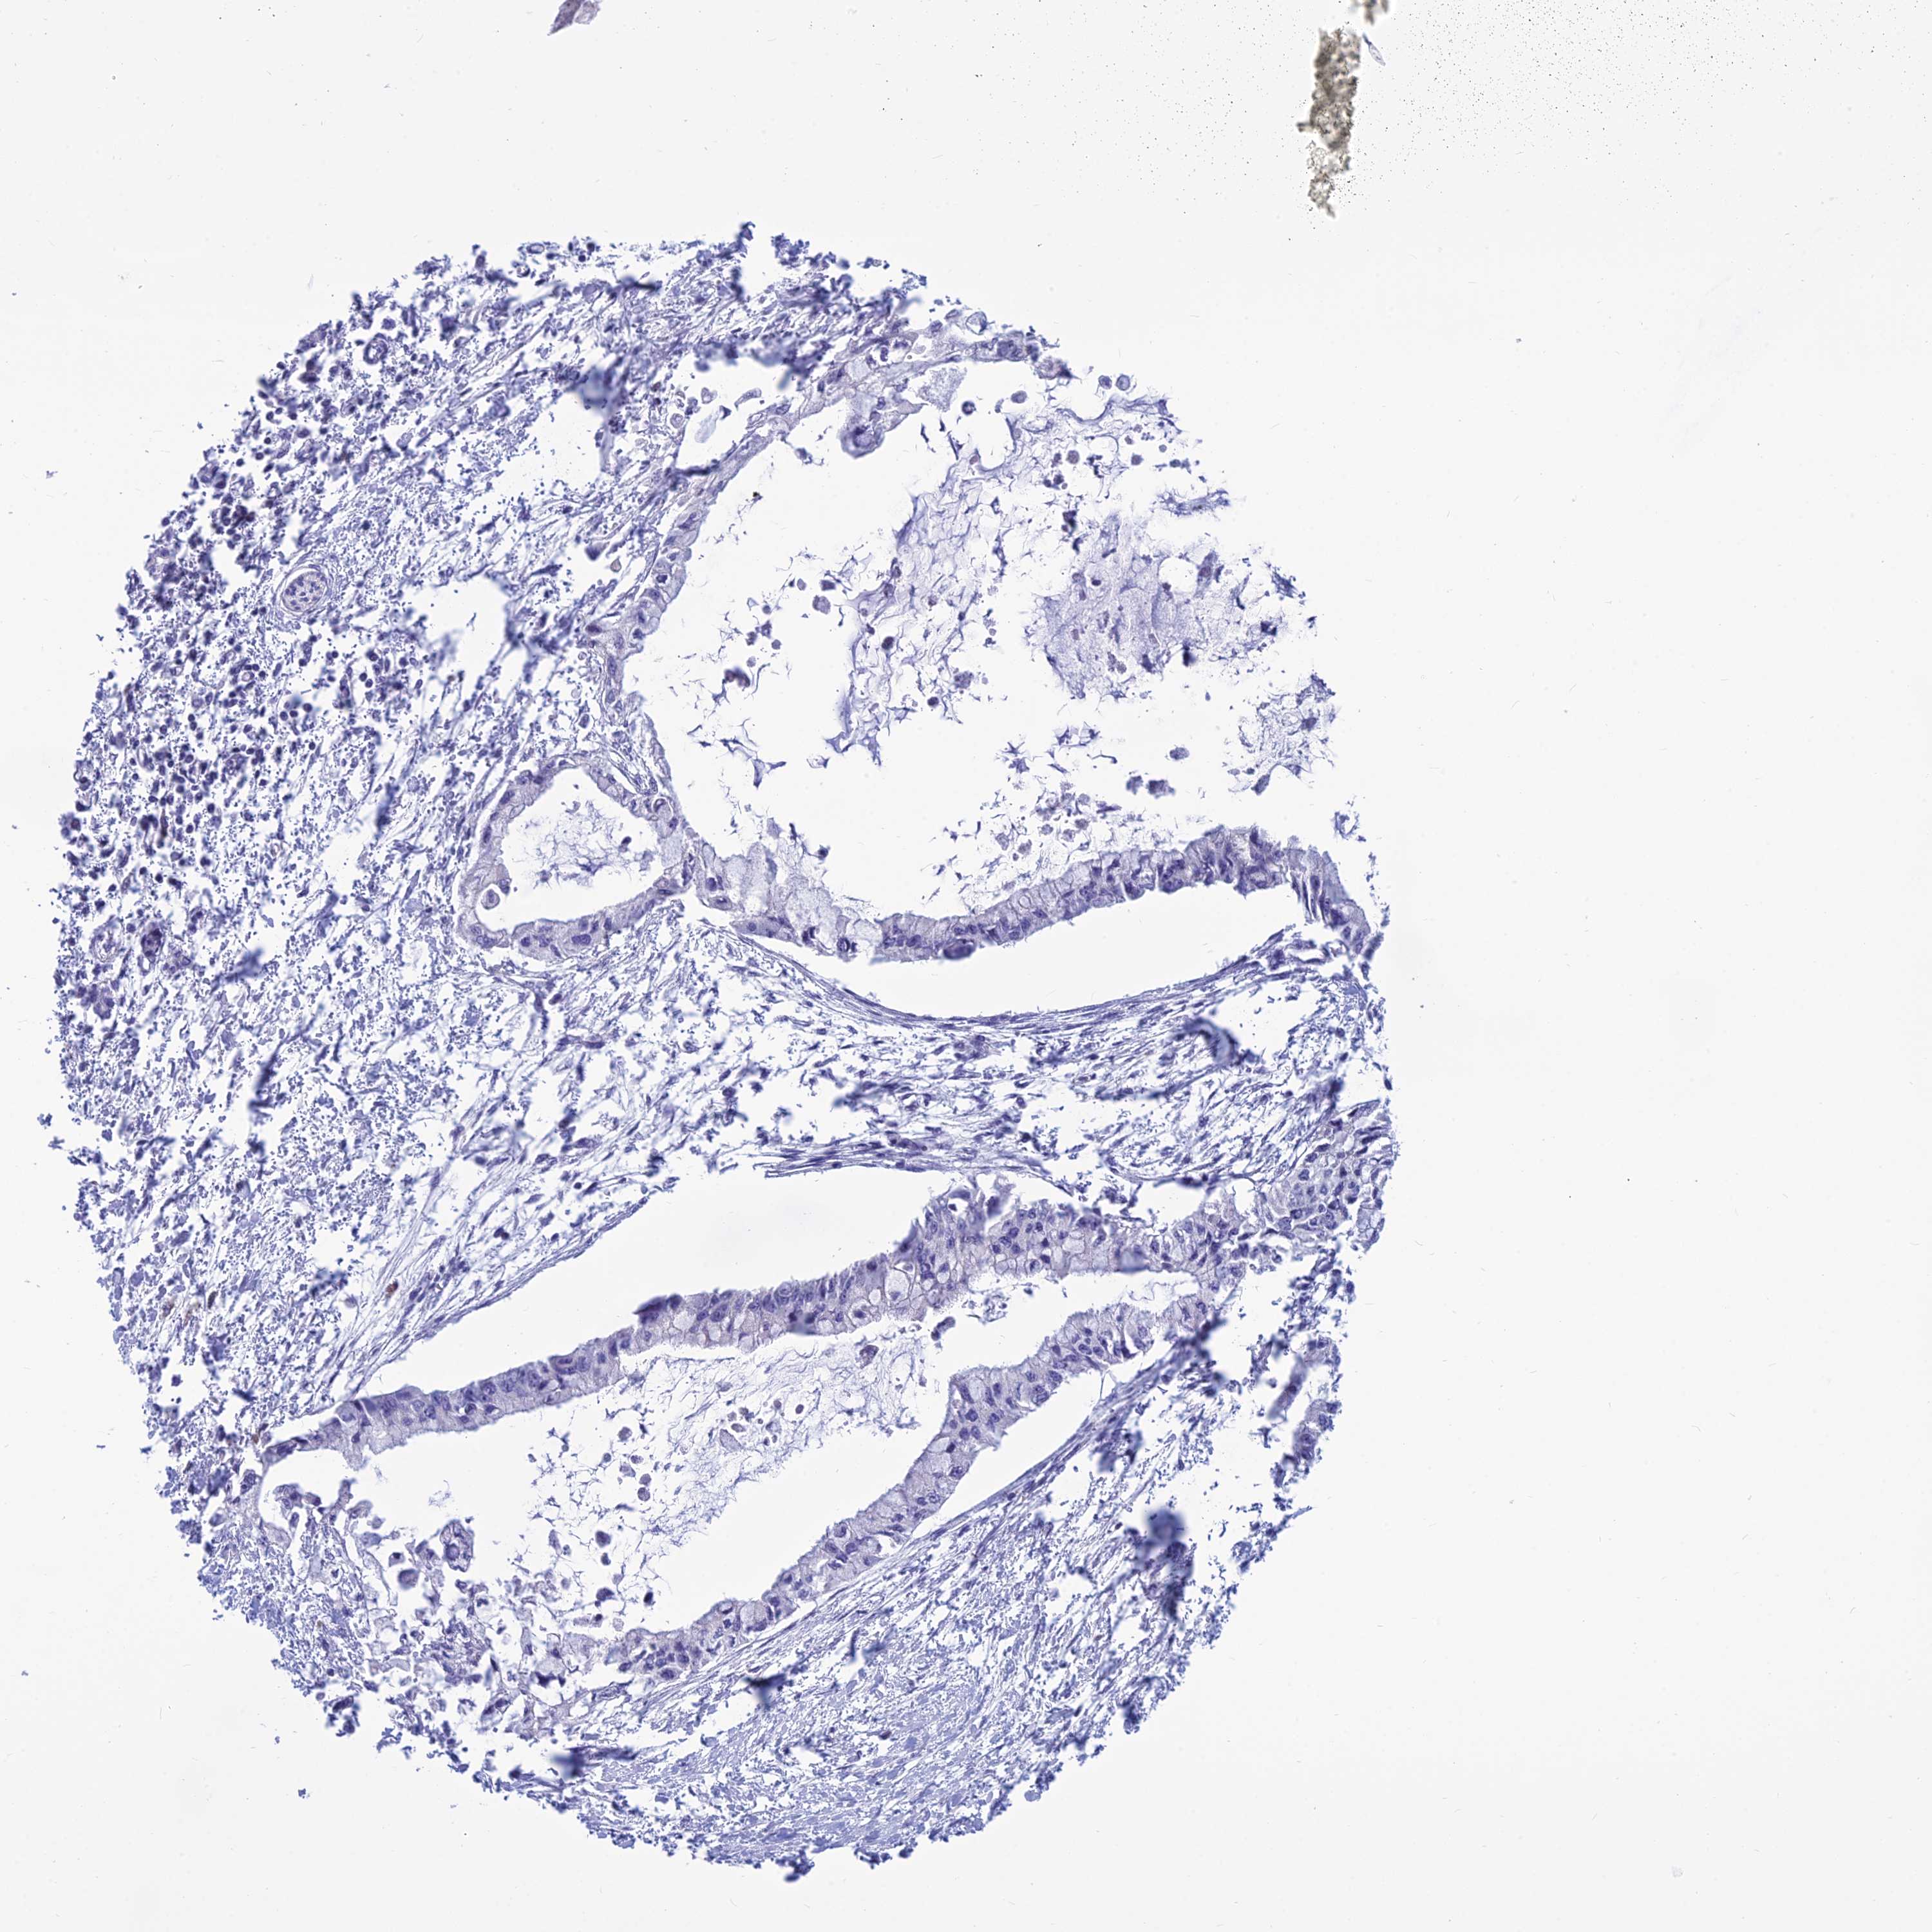

PANCREATIC CANCER - Protein expressioni

A mouse-over function shows sample information and annotation data. Click on an image to view it in a full screen mode. Samples can be filtered based on level of antibody staining by selecting one or several of the following categories: high, medium, low and not detected. The assay and annotation is described here.

Note that samples used for immunohistochemistry by the Human Protein Atlas do not correspond to samples in the TCGA dataset.

Antibody stainingi

Antibody staining in the annotated cell types in the current human tissue is reported as not detected, low, medium, or high, based on conventional immunohistochemistry profiling in selected tissues. This score is based on the combination of the staining intensity and fraction of stained cells.

Each image is clickable and will lead to virtual microscopy that enables deeper exploration of all samples and also displays staining intensity scores, fraction scores and subcellular localization as well as patient and tissue information for each sample.

Antibody HPA044573

Staining

High

Medium

Low

Not detected

Intensity

Strong

Moderate

Weak

Negative

Quantity

>75%

75%-25%

<25%

None

Location

Nuclear

Cytoplasmic/membranous

Cytoplasmic/membranous,nuclear

Adenocarcinoma, NOS